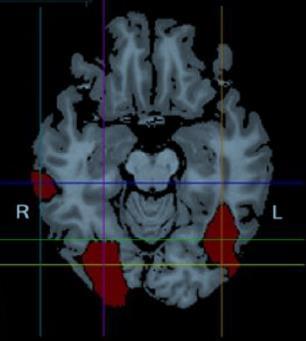

El 14 de agosto de 1992, Pierrette Sapey (P.S.) fue golpeada violentamente en su cabeza por un espejo de un autobús londinense produciéndole una herida cerrada en la cabeza.

IOG Circunv. fusiforme Tomado de Rossion, B., (2022). Neuropsychologia., 173, 108278.

Como consecuencia del daño cerebral extenso, perdió para siempre la habilidad de reconocer la identidad de la gente por sus caras (prosopagnosia; del griego “prosopon”, cara y “a-gnosia”, sin conocimiento). Pero podía reconocer otros objetos como animales, frutas o vegetales.

La función visual de bajo nivel (agudeza visual, sensibilidad al contraste y visión del color) está bien preservada. PS tiene un escotoma paracentral izquierdo de 2-3º.

Tomado de Rossion, B., (2022). Neuropsychologia., 173, 108278.